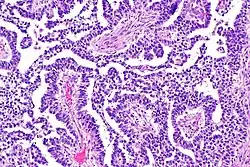

Yolk sac tumor

The ovarian yolk sac tumors, also known as endodermal sinus tumors, are accountable for approximately 15.5% of all OGCTs.[8] They have been observed in women particularly in their early ages, and rarely after 40 years of age.[9] The critical pathologic features are a smooth external surface and capsular tears due to their rapid rate of growth. A study consisting of 71 individual cases of ovarian yolk sac tumor provides evidence to the proliferation of the tumor. In one of the cases, the pelvic examination revealed normal activity until a 9 cm and 12 cm sized tumor was discovered 4 weeks later.[9] In another case, a 23 cm tumor was discovered in a pregnant woman who was monitored regularly and had normal findings until oophorectomy became essential.[9] Histologically, these tumors are characterized by mixed solid and cystic components.[1] The mixed solid components are characterized by a soft gray to yellow solid components accompanied with significant hemorrhage and necrosis. The cysts are approximately 2 cm in diameter and populated throughout the tissue which results in giving the neoplasm a ‘honeycombed appearance’.[1]